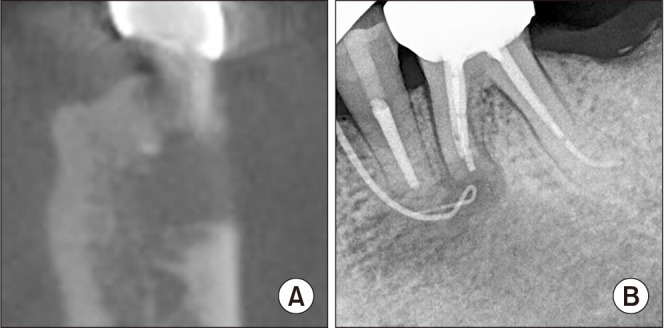

Results: A total of 147 teeth was included in this study. All the operated teeth underwent preoperative root canal treatment by an endodontic specialist. Apicoectomy was performed for 119 inflammatory cysts and 28 non-inflammatory cysts. Retrograde filling was performed on 22 teeth with inflammatory cysts and 3 teeth with non-inflammatory cysts. All teeth survived the 3.5-year follow-up (range, 1.0-9.1 years). However, 1 tooth with an inflammatory cyst developed complications 1 year after surgery that required re-endodontic treatment.